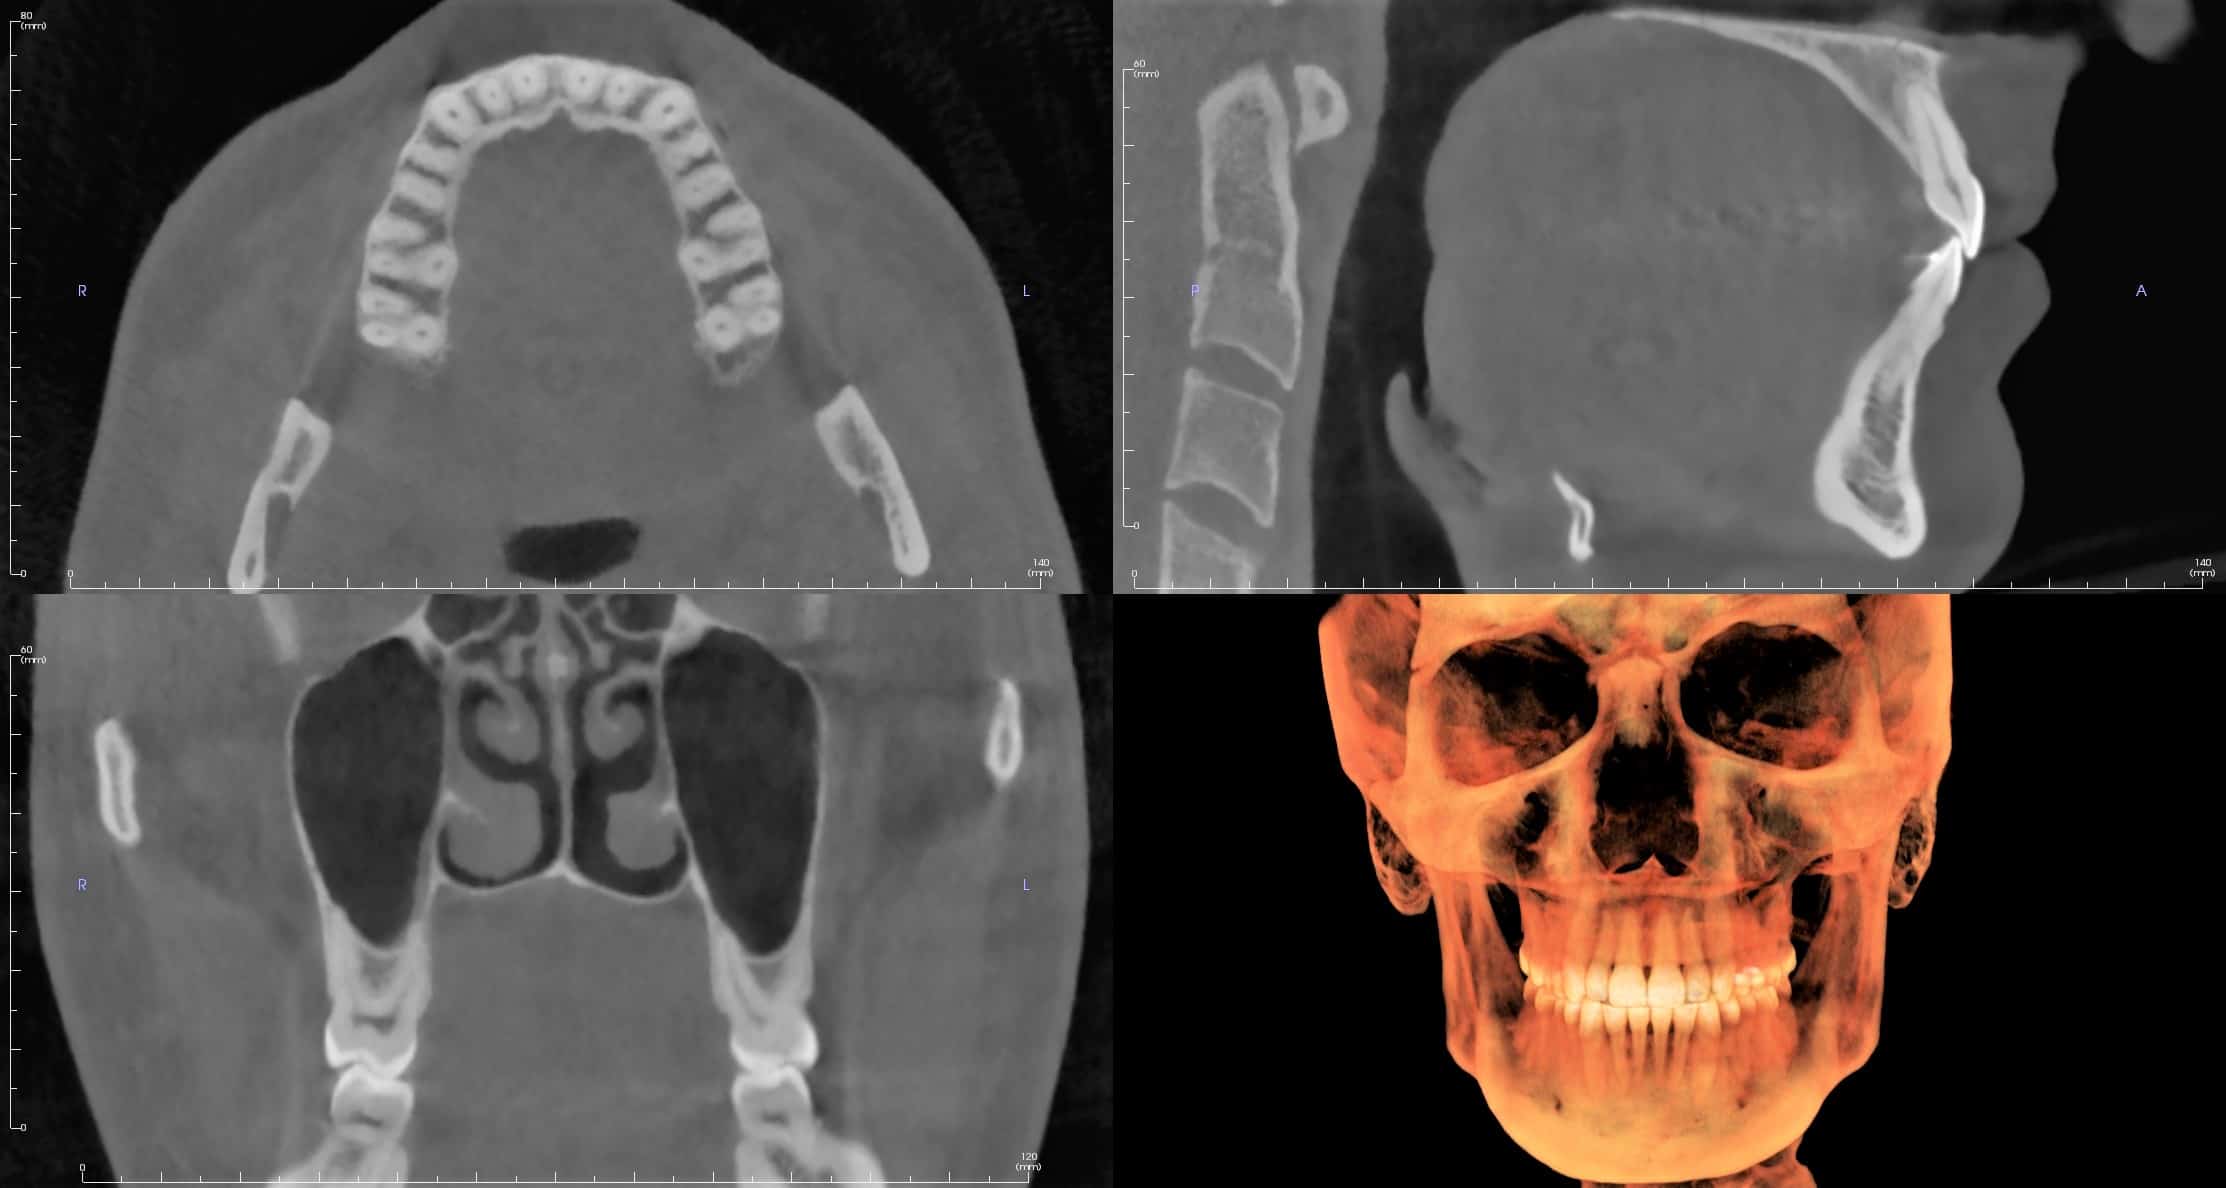

Cone-Beam CT

A legmodernebb fogászati, szájsebészeti céllal kifejlesztett digitális diagnosztikus eljárás. Előnye a hagyományos CT vizsgálathoz képest, hogy sokkal kisebb sugárterheléssel jár. Hátránya, hogy a lágyrészek pontos megítélésére nem alkalmas, de diagnosztizálhatók vele a csontos eltérések és az állkapocsizület esetleges rendellenességei is

Implantációs fogpótlásoknál, csontpótlásoknál, arcüreg műtéteknél alapvető fontosságú. Az orvos ennek segítségével teljes pontossággal megtudja tervezni a beavatkozást, sőt az adatok különleges számítógépes segédprogramokkal történő feldolgozásával a végleges fogpótlást is. CT vezérelt implantáció esetén használata elengedhetetlen. Alkalmazásával a csont mennyisége, minősége, és a környező anatómiai képletek (idegek, arcüreg stb.) elhelyezkedése tökéletesen megítélhető, mérhető.